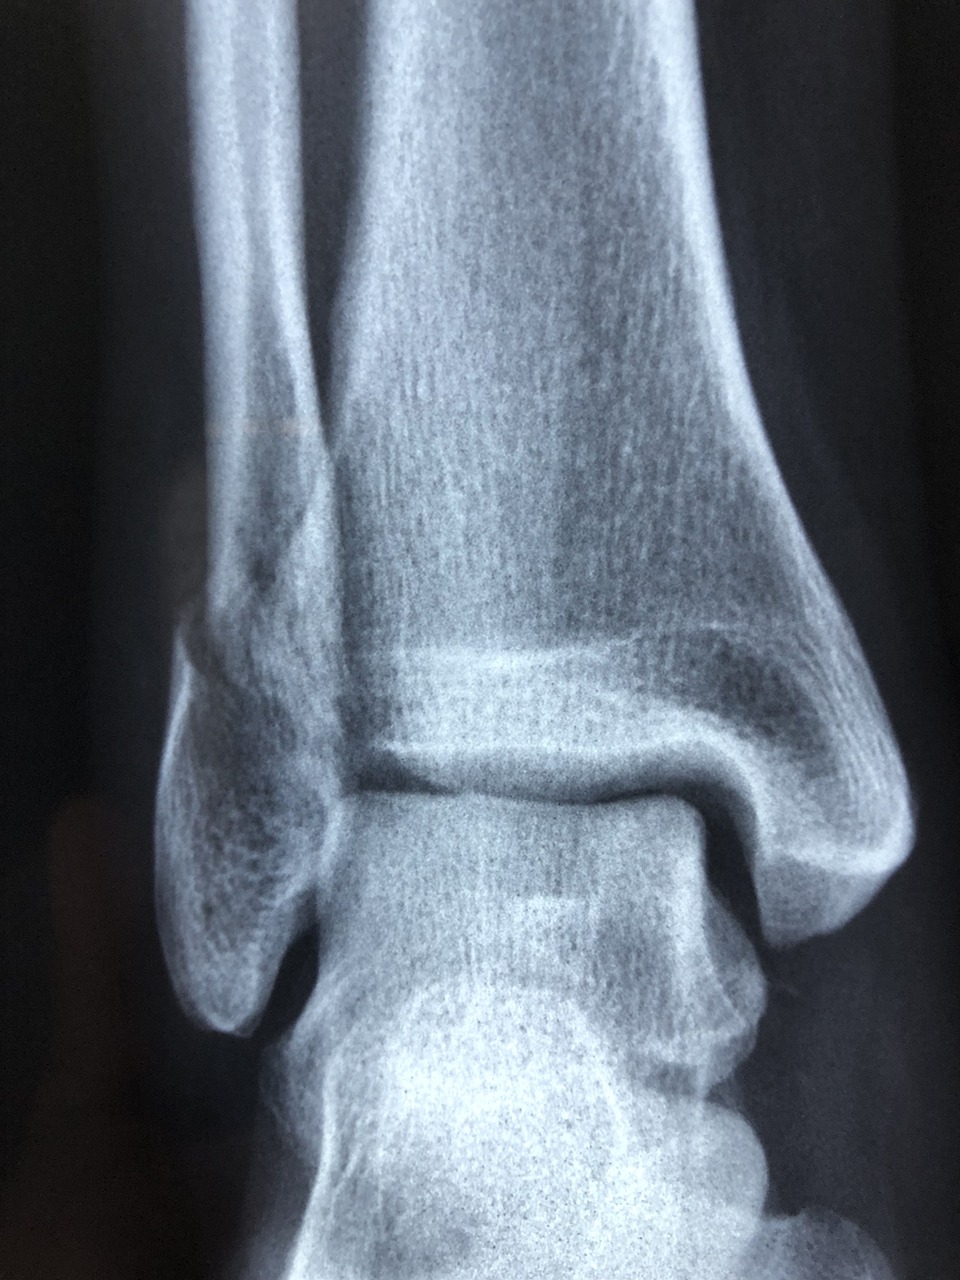

2) 영상 검사

- 단순 X-ray 촬영으로 종양의 위치와 크기, 골파괴 정도를 확인합니다.

- CT 스캔은 종양의 정확한 범위와 침범 정도를 평가하는데 도움이 됩니다.

- MRI 검사는 연부 조직 침범 여부를 확인할 수 있습니다.

- 골 스캔은 전신 골 전이 여부를 확인하는데 사용됩니다.

영상 검사(X-ray, MRI, PET-CT 등)를 통해 빠른 진단이 가능합니다.